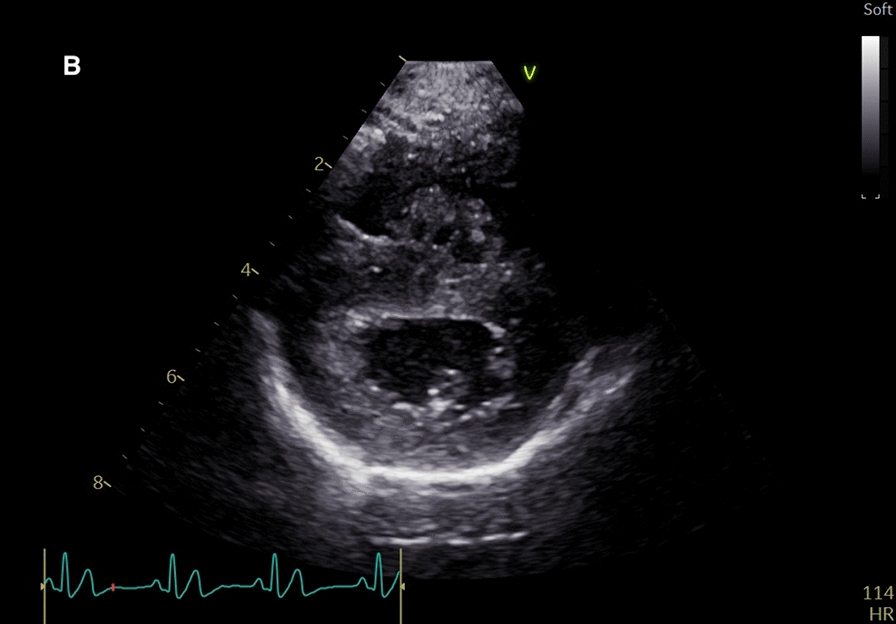

A fifteen-month-old Pembroke Welsh corgi with respiratory distress, exercise intolerance, and moderate regenerative anemia was referred to The Norwegian University of Life Sciences, Small Animal Hospital.Hematology revealed moderate regenerative anemia without evidence of hemolysis. Thoracic radiographs showed a generalized mixed interstitial to alveolar lung pattern and enlarged pulmonary arteries. Changes suggestive of moderate pulmonary hypertension were noted on echocardiography. Baermann fecal diagnostic flotation identified large numbers of Angiostrongylus vasorum larvae, and the AngioDetect serological antigen test was positive. The dog was treated with a two-week course with fenbendazole (51 mg/kg q24h po) and topical imidacloprid/moxidectin (250 mg/62.5 mg) and a one-week course with sildenafil (0.45 mg/kg q12h po). Complete clinical, clinicopathological and echocardiographic resolution was observed after only four weeks. Rapid improvement of echocardiographic abnormalities in cases with suspected pulmonary hypertension is not usually reported in cases with angiostrongylosis.Infection with A. vasorum should be considered in dogs with respiratory signs and bleeding tendencies, even in countries with no endemic history or reported cases.